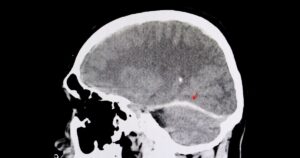

Traumatic brain injuries (TBIs) are a serious concern following truck accidents, yet they are often overlooked because symptoms may not appear immediately. Any significant impact or sudden, violent motion can cause the brain to move within the skull, potentially leading to injury. Even if you feel fine immediately after a crash, it does not mean […]

Why Traumatic Brain Injuries Are Common but Often Overlooked After Truck Accidents